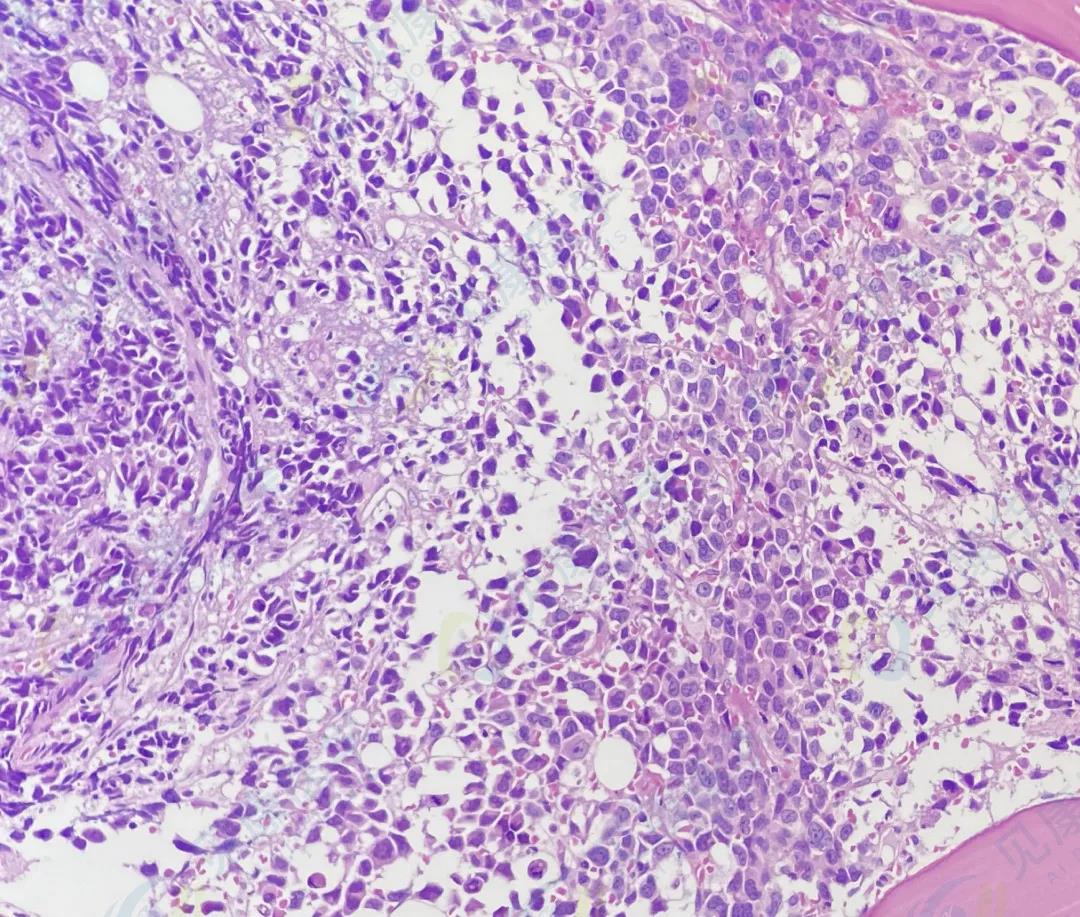

HE

诊断结果

多发性骨髓瘤